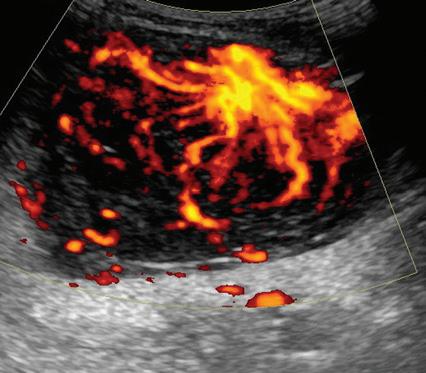

Most ultrasound machines include color and power Doppler imaging capabilities, with possible spectral waveform analysis. Ultrasound uses the Doppler effect, in which the sound frequency of an object changes as the object travels toward or away from a point of reference, to obtain information about blood flow. Color flow imaging shows

colored blood flow superimposed on a gray-scale image, in which two colors such as red and blue represent flow toward and away from the transducer, respectively (Fig. 1.28).24 Pulsed-wave or duplex Doppler ultrasound displays an ultrasound image and waveform (Fig. 1.29). There are important considerations to optimize the Doppler ultrasound. Reducing the width of the field of view and increasing the frame rate are helpful. To correct for aliasing (when the Doppler shift frequency of blood is greater than the detected frequency, which causes an error in frequency measurement), one can increase the pulse repetition frequency, lower the ultrasound frequency, or increase the angle between the sound beam

FIGURE 1.28 Color Doppler: Schwannoma. Color Doppler ultrasound image shows increased blood flow in hypoechoic peripheral nerve sheath tumor.

and the flow direction toward perpendicular. Power Doppler is another method of color Doppler ultrasound that is generally considered more sensitive to blood flow (it shows small vessels and slow flow rates) compared with conventional color Doppler, although significant variability exists depending on the ultrasound machine.25 Unlike conventional color Doppler, power Doppler assigns a color to blood flow regardless of direction (Fig. 1.30) and is extremely sensitive to movement of the transducer, which produces a flash artifact. The color gain should be optimally adjusted for Doppler imaging to avoid artifact if the setting

is too sensitive and for false-negative flow if sensitivity is too low. To optimize power Doppler imaging, set the color background (without the gray-scale displayed) so that the lowest level of color nearly uniformly is present, with only minimal presence of the next highest color level.26

Increased blood flow on color or power Doppler imaging may occur with increased perfusion, inflammation, and neovascularity. In imaging soft tissues, color and power Doppler imaging are used to confirm that an anechoic tubular structure is a blood vessel and to confirm blood flow. When a mass is identified, increased blood

FIGURE

flow may suggest neovascularity, possibly from malignancy (Fig. 1.31).27 Although the finding is nonspecific, a tumor without flow is more likely to be benign, and malignant tumors usually demonstrate increased flow and irregular vessels.28 With regard to superficial lymph nodes, either no flow or hilar flow is more common with benign lymph node enlargement, and spotted, peripheral, or mixed patterns of flow are more common with malignant lymph node enlargement (see Chapter 2).29 Color or power Doppler imaging is also helpful in the differentiation between complex fluid and a mass or synovitis; the former typically has no internal flow, and the latter may show increased flow.30 After treatment for inflammatory

FIGURE 1.30 Power Doppler: Schwannoma. Power Doppler ultrasound image shows increased blood flow in hypoechoic peripheral nerve sheath tumor.